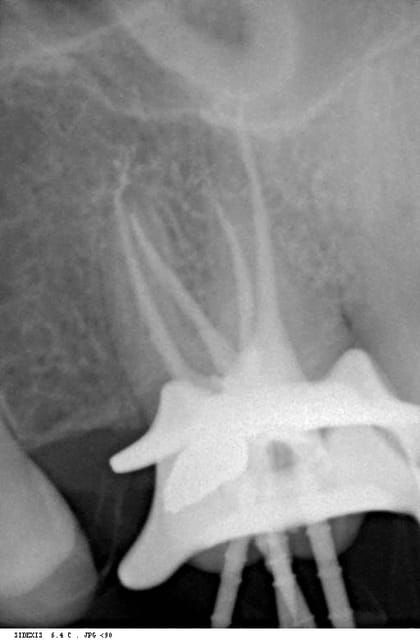

bé oui, j'ai bien compris ta manoeuvre pour le canal P, je te parle du canal MV un peu avant la courbure.

Tu penses faire un ICC car tu as aussi laissé un vide en coronaire dans la racine DV???

yep, même que l'empreinte a été prise dans la foulée, de la gutta...

oh,le beau faux canal ! c'est pas grave si on en trouve que trois quelquefois!

Oui,mais dans ce cas à quoi servent les photos? et

comment peut on prouver la bonne désinfection,ça passe pas à l'image,mise à part le tracé de la préparation